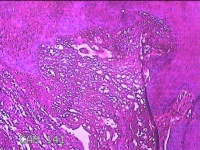

下唇肿物

性别

男

年龄

22岁

临床诊断

口腔黏液腺囊肿

一般病史

下唇肿物一个月余。

标本名称

大体所见

灰白粉红色带皮肤样肿物1x0.3x0.2cm一堆,表面光滑,切开肿物呈实性,切面灰白粉红色,质软。

图2